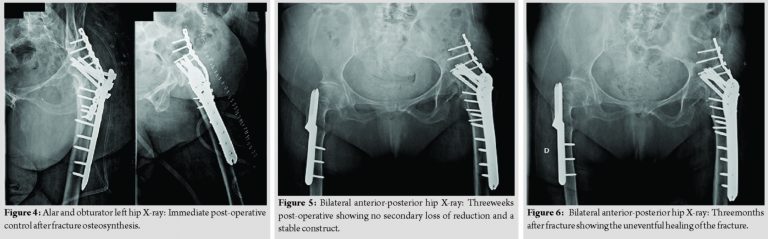

After carefully assessing scientific evidence and discussing the appropriate treatment strategy, the patient was prepared for surgery. She was positioned in lateral decubitus and a lateral approach was used, centered on the great trochanter. The fracture was exposed and fixated with two plates. One proximal locking femoral plate, with 6mm×4.5 mm cortical and 4mm×6.5 mm cannulated screws, was applied to the head and proximal femur. Expecting a great stress in the fracture site, this construction was reinforced with a 3.5 mm pelvic reconstruction plate, with 8mm×3.5 mm cortical screws, spanning from the iliac wing to the proximal femur (Fig. 3 and 4). Due to the poor bone quality and the unusual long lever arm, the patient was not permitted to walk until 3 weeks after the intervention (Fig. 5) and only partial weight-bearing afterward. Bone healing occurred after 3 months, allowing the patient to walk with a single cane and full weight-bearing (Fig. 6).

When presented with a common proximal femoral fracture, we can consider the femoral head as one unit and the trochanteric area as another. This means that when we fix it, the disruption forces will be between the head and proximal femur. In the case presented here, this is not true. Since the hip is fused, the left hemipelvis works with the femur as a single unit. After the fracture, the left hemipelvis together the femoral head will be the proximal component of the fracture. In this scenario, the lever arm and stress generated at the fracture site are higher than in the common trochanteric fractures. Having this in mind, the authors assumed that it could not be fixed in the usual way. With the typical components – DHS®, nail, and PFLP – the fixation would be between the proximal femur and the femoral head. Therefore, since the left hemipelvis and femoral head act as a single unit, most of the proximal fracture component would not be fixed and stabilized into the construction. The long lever arm would impose a huge stress into the construction, making it likely to fail. To overcome this problem, the authors decided to reinforce and extend the construction from the iliac wing to the proximal femur. This was accomplished by adding an extrapelvic reconstruction plate to the proximal locking femoral plate (Fig. 3 and 4). The authors also discussed the conversion to a THA as a possible treatment. Although technically demanding, this approach is possible. Nevertheless, some key points were taken into consideration: Reports of conversions to a THA are usually worse than primary THA due to osteonecrosis; the poor quality of abductor musculature after 53 years of the hip fusion; the patient age; and her expectations. Therefore, despite providing the patient with a long-lost hip mobility, the conversion was not considered a viable option for this case.

There are very few cases reported in literature about fractures involving an ankylosed hip. There is no optimal treatment established for these situations, and as mentioned before, each surgeon had a different approach and choice of implants, with its pros and cons. In this report, the authors considered the left hemipelvis and femoral head as one unit, therefore, creating a long lever arm and submitting the fracture site to a huge stress, which implies that the fixation must be strong enough to overcome it. Conversion to a THA was possible, although technically demanding and with worse results than primary hip replacement. In this situation, this approach was excluded due to the age of the patient and the low quality of the abductor musculature. Using two plates into the construction, spanning from the hemipelvis to the proximal femur, the authors provided enough strength and stability to overcome the unusual long lever arm and allowed the fracture to heal uneventful after 3months. With this case, it is presented a different and viable approach to a rare fracture presentation, which can be easily reproduced and can be considered in similar patients.